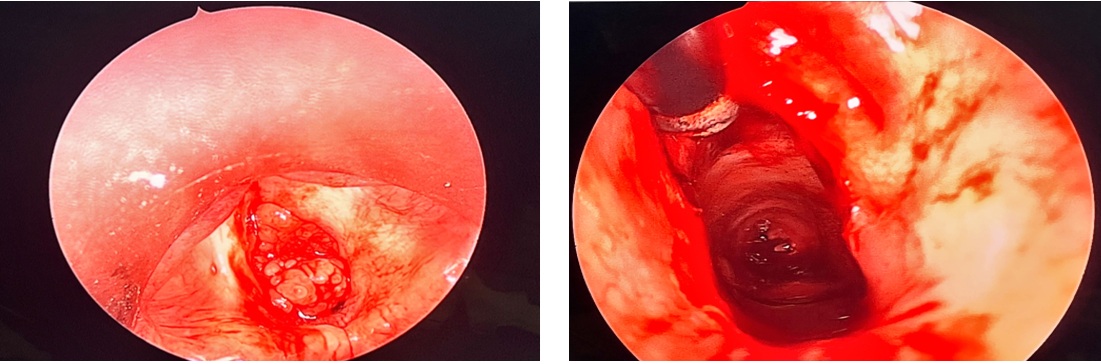

Hình 3. Hình ảnh Papilloma trên nội soi

Nội soi họng: Khối papilloma màu hồng, dạng sùi nhiều thùy, bề mặt không chảy máu, chiếm gần trọn thanh môn.

- Tiến hành phẫu thuật: hình ảnh vi phẫu thanh quản cắt u, làm thông thoáng đường thở, kiểm soát chảy máu

Hình 7. Phẫu trường